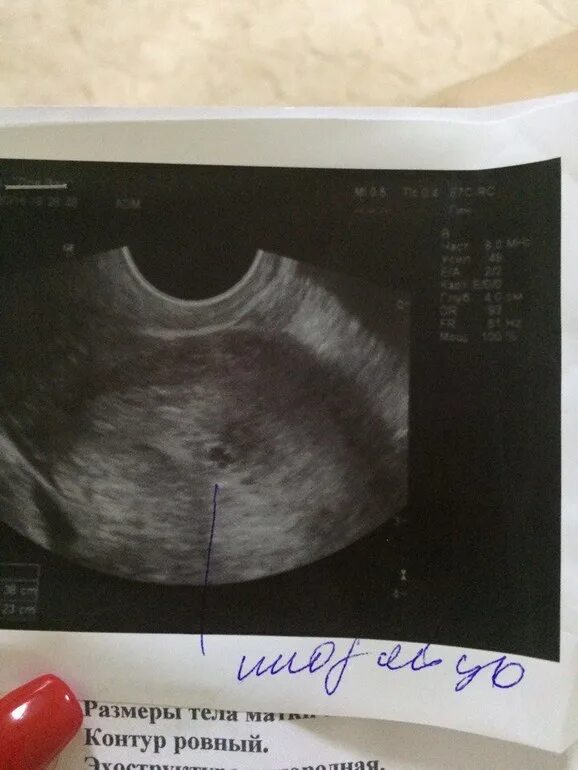

Плодное яйцо 4